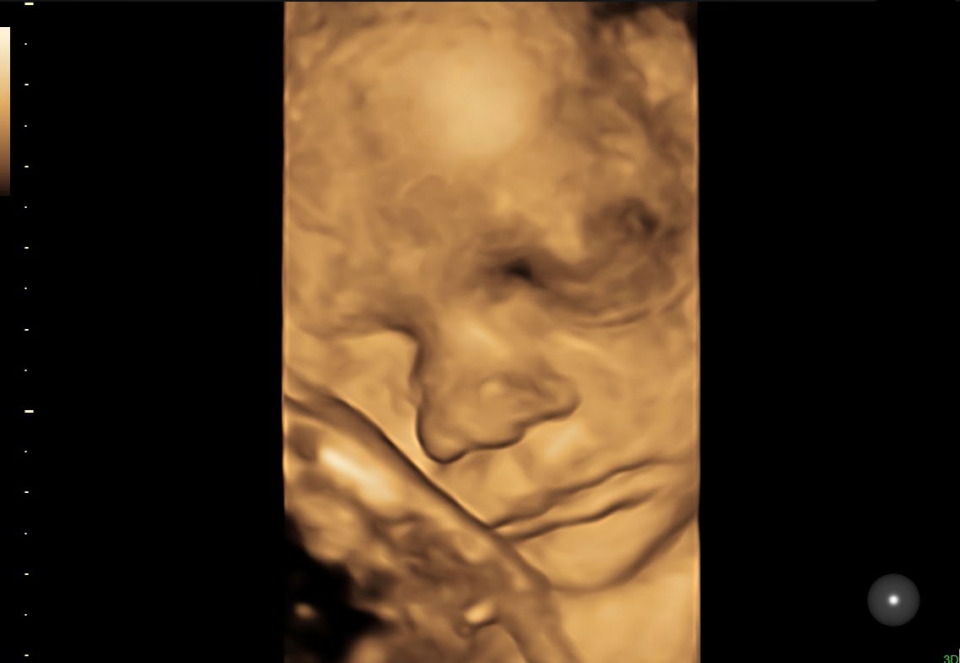

УЗИ аппарат Voluson S10 позволяет проводить обследования высочайшего уровня с максимальной точностью диагностики. Благодаря технологии Voluson Core Architecture достигнут высокий уровень качества изображений с возможностью последующей обработки и анализа даже после проведения скрининга. Технология HDlive делает изображения удивительно реалистичными и объемными.

• HDlive в 3D и 4D - режим перемещаемого виртуального источника освещения - "виртуальная фетоскопия"